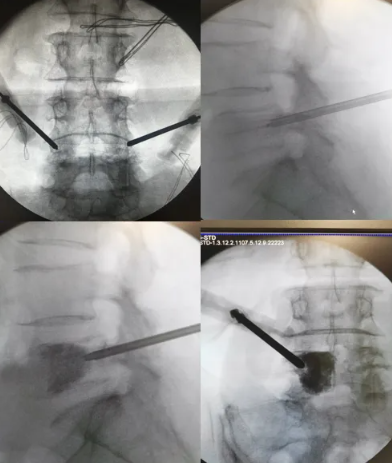

·患者凌某某,女,65岁,因反复腰背部疼痛半年余入院。腰背痛VAS评分6分。

·诊断:1.腰5椎体转移瘤(ESCC,0级);2.直肠癌

首例局麻下智能控温射频消融联合椎体成形术治疗脊柱转移瘤

患者手术全程保持清醒,射频消融过程中无任何不适。术后第一天佩戴腰围起床活动。术后腰背痛VAS评分3分。